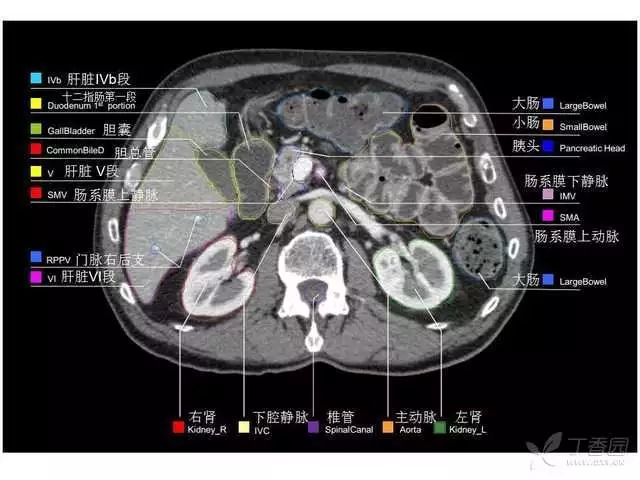

腹部肝脏高清CT断层的图谱

全腹部高清CT图谱,淋巴结彩色图谱,血管解剖图谱大汇总!

肝段,肝内管道的分布规律